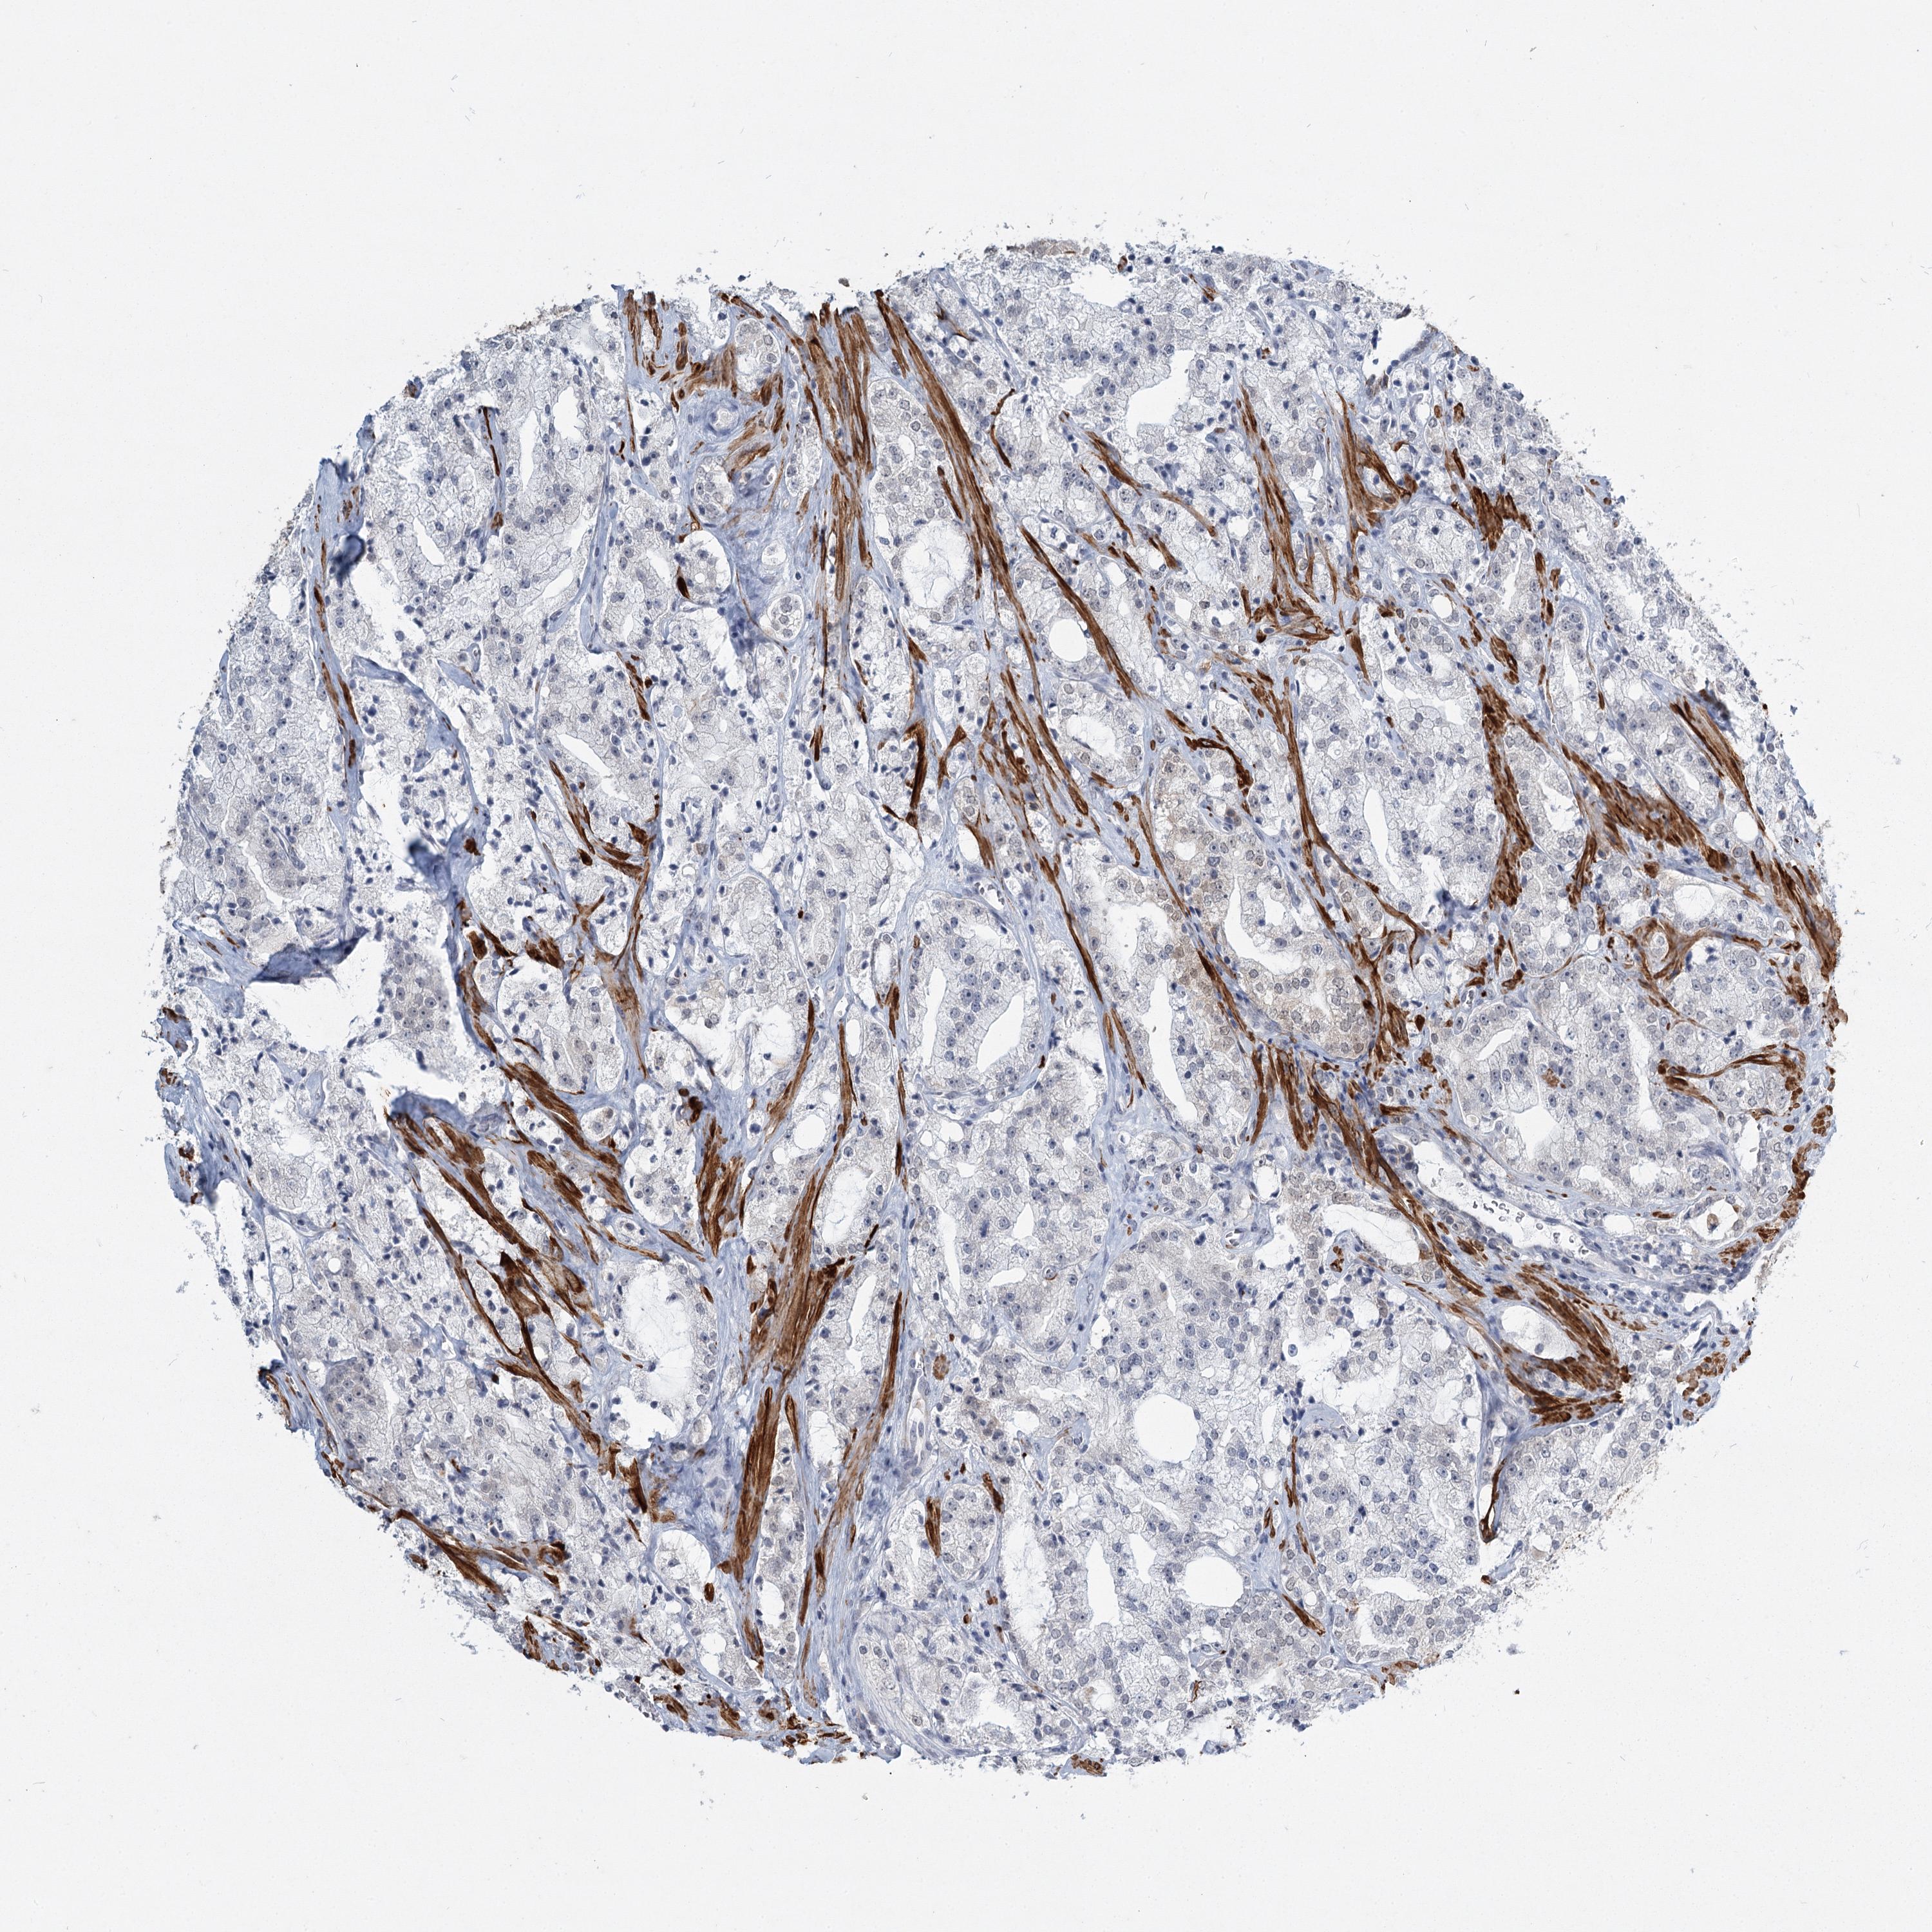

PROSTATE CANCER - Protein expressioni

A mouse-over function shows sample information and annotation data. Click on an image to view it in a full screen mode. Samples can be filtered based on level of antibody staining by selecting one or several of the following categories: high, medium, low and not detected. The assay and annotation is described here.

Antibody stainingi

Antibody staining in the annotated cell types in the current human tissue is reported as not detected, low, medium, or high, based on conventional immunohistochemistry profiling in selected tissues. This score is based on the combination of the staining intensity and fraction of stained cells.

Each image is clickable and will lead to virtual microscopy that enables deeper exploration of all samples and also displays staining intensity scores, fraction scores and subcellular localization as well as patient and tissue information for each sample.

Antibody HPA023187

Antibody CAB034226

Staining

High

Medium

Low

Not detected

Intensity

Strong

Moderate

Weak

Negative

Quantity

>75%

75%-25%

<25%

None

Location

Nuclear

Cytoplasmic/membranous

Cytoplasmic/membranous,nuclear

Adenocarcinoma, High grade

Adenocarcinoma, Low grade

Adenocarcinoma, NOS